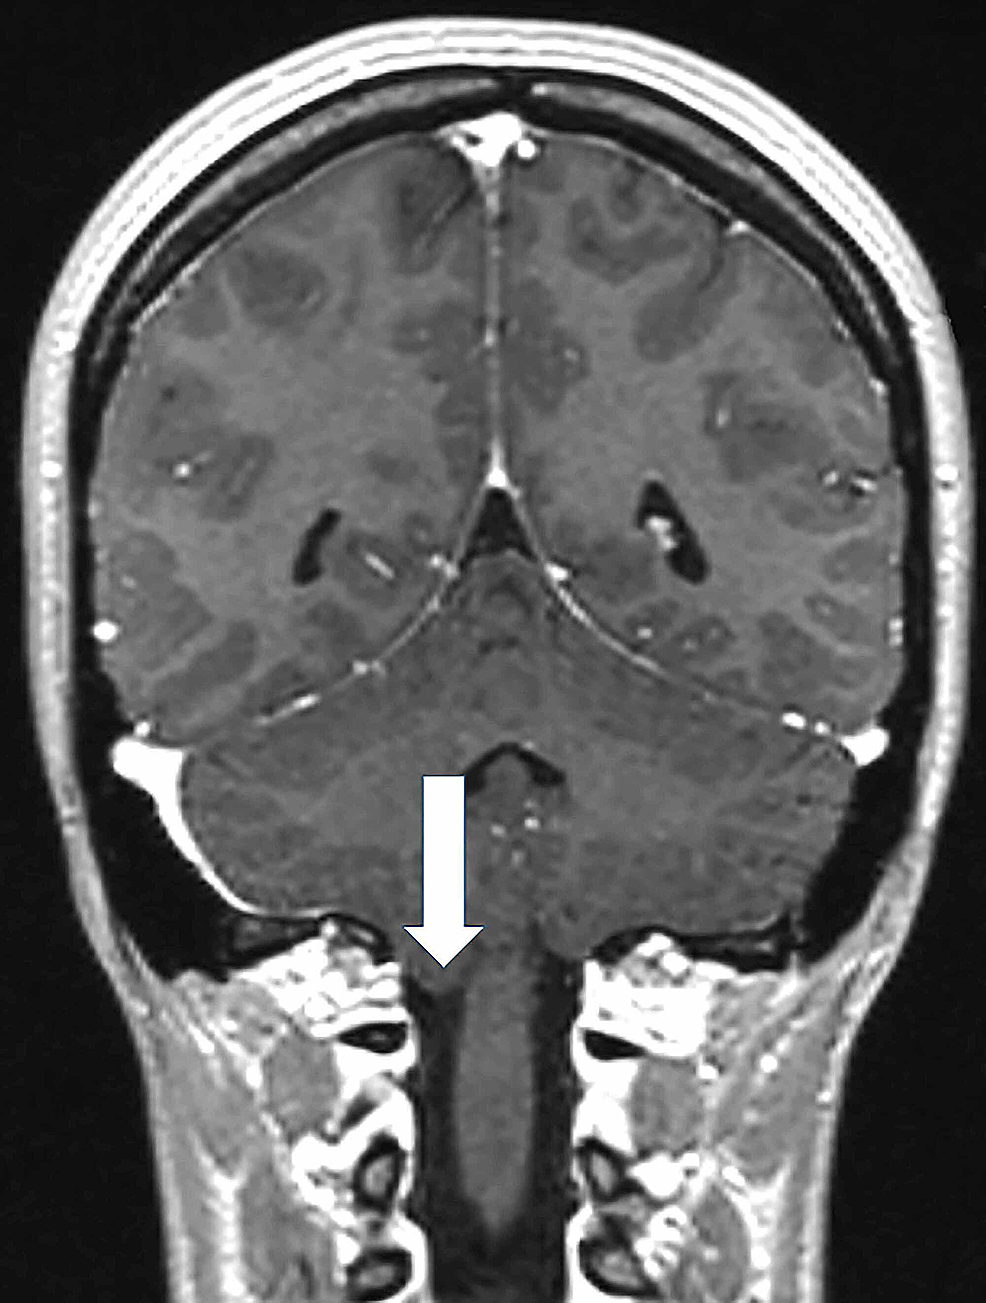

As neuro-otological examination was unremarkable, a central nervous system involvement was suspected. For this reason a contrast-enhanced MRI of the brain was performed. The MRI revealed a cerebellar tonsil herniation through the foramen magnum configuring CIM, without syringomyelia (Figure 2).